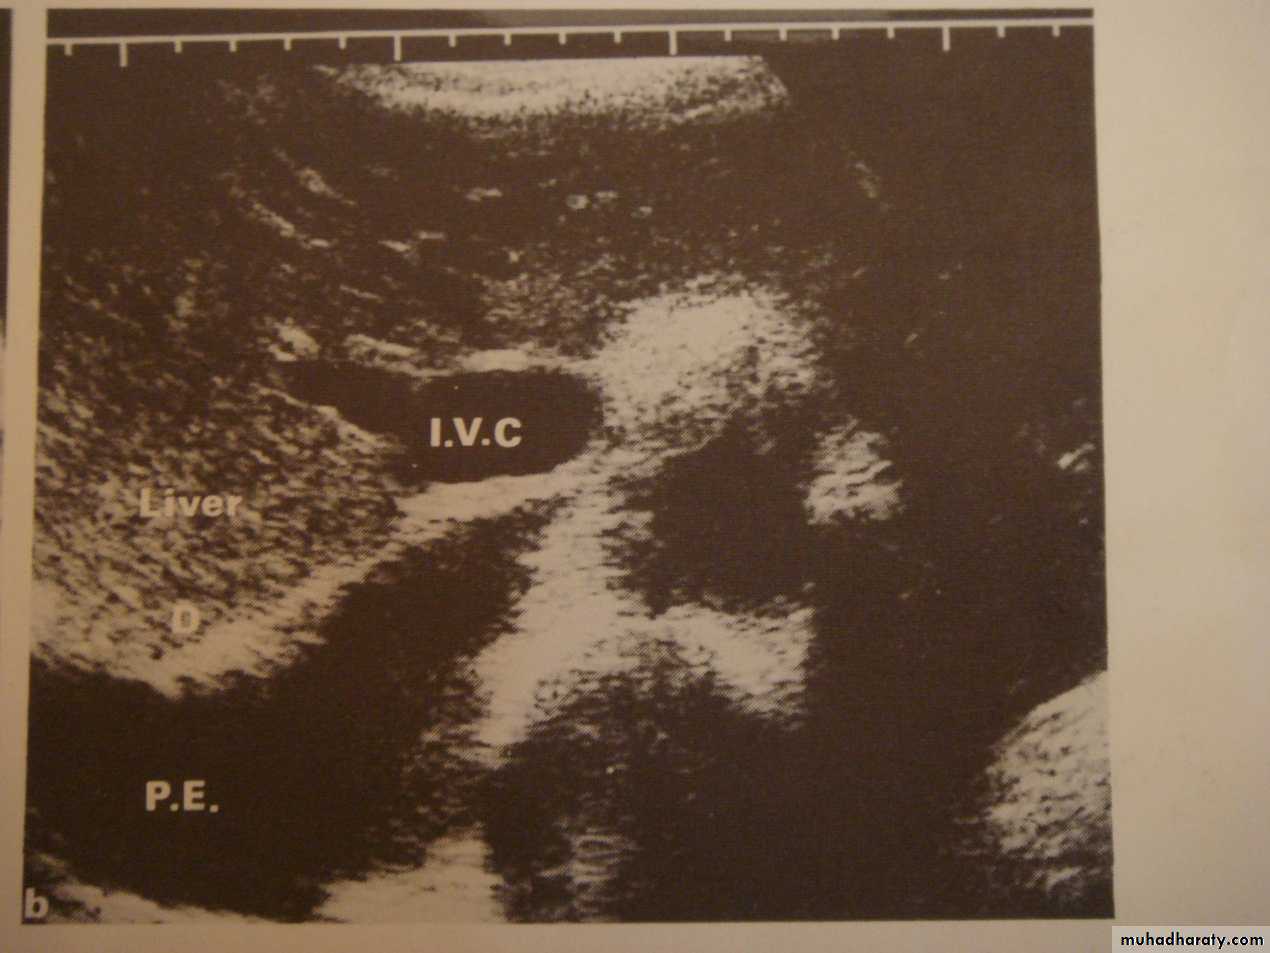

3-US: has limited role in chest imaging due to lungs gases and chest wall bones, but helpful in assessment of pleural effusion, peripheral lung lesions, pleural masses, chest wall masses, diaphragmatic movement, guided procedures and differentiating solid from cystic lesions.

• Pleural effusion : collection of fluid within the pleural space. This can be further divided into Transudate , exudate, according to protein content .Other type of fluid collection within pleural space are

A subpulmonic effusion

(infrapulmonary effusion) accumulation of fluids between the lung & visceral pleura ..The following features are helpful :elevation of the hemidiaphragm ..right: peak of the hemidiaphragm is shifted laterally

left: increased distance between lower lobe air and gastric air bubble